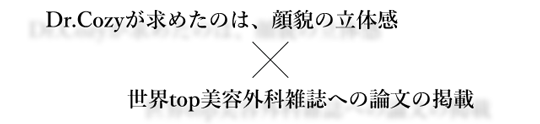

キラキラした笑顔は

芸能人だけの特権ではない

美容外科の世界的トップジャーナルである

アメリカ形成外科学会

Plastic Reconstructive Surgeryの

OA版に考案した治療方法が掲載されました。

世界に認められた治療法

A点手術は世界的な権威のある論文に掲載され、

世界に認められた治療として確立しています。

A点手術

チタンプレートを用いて

鼻の下を前方に出すことで、

1)顔の立体感

2)加齢により後ろに下がる鼻下部分の改善

を目的とした治療になります。

A点+α手術

A点手術に改良を加えて人工真皮とプレートを鼻翼基部に移植することで、より顔貌の立体感を得ることができる治療になります。